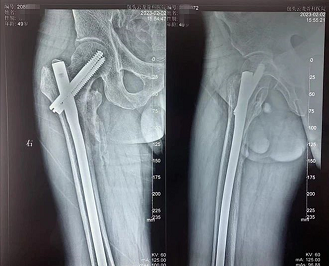

老年髋部骨折的典型术式—PFNA固定股骨粗隆间骨折